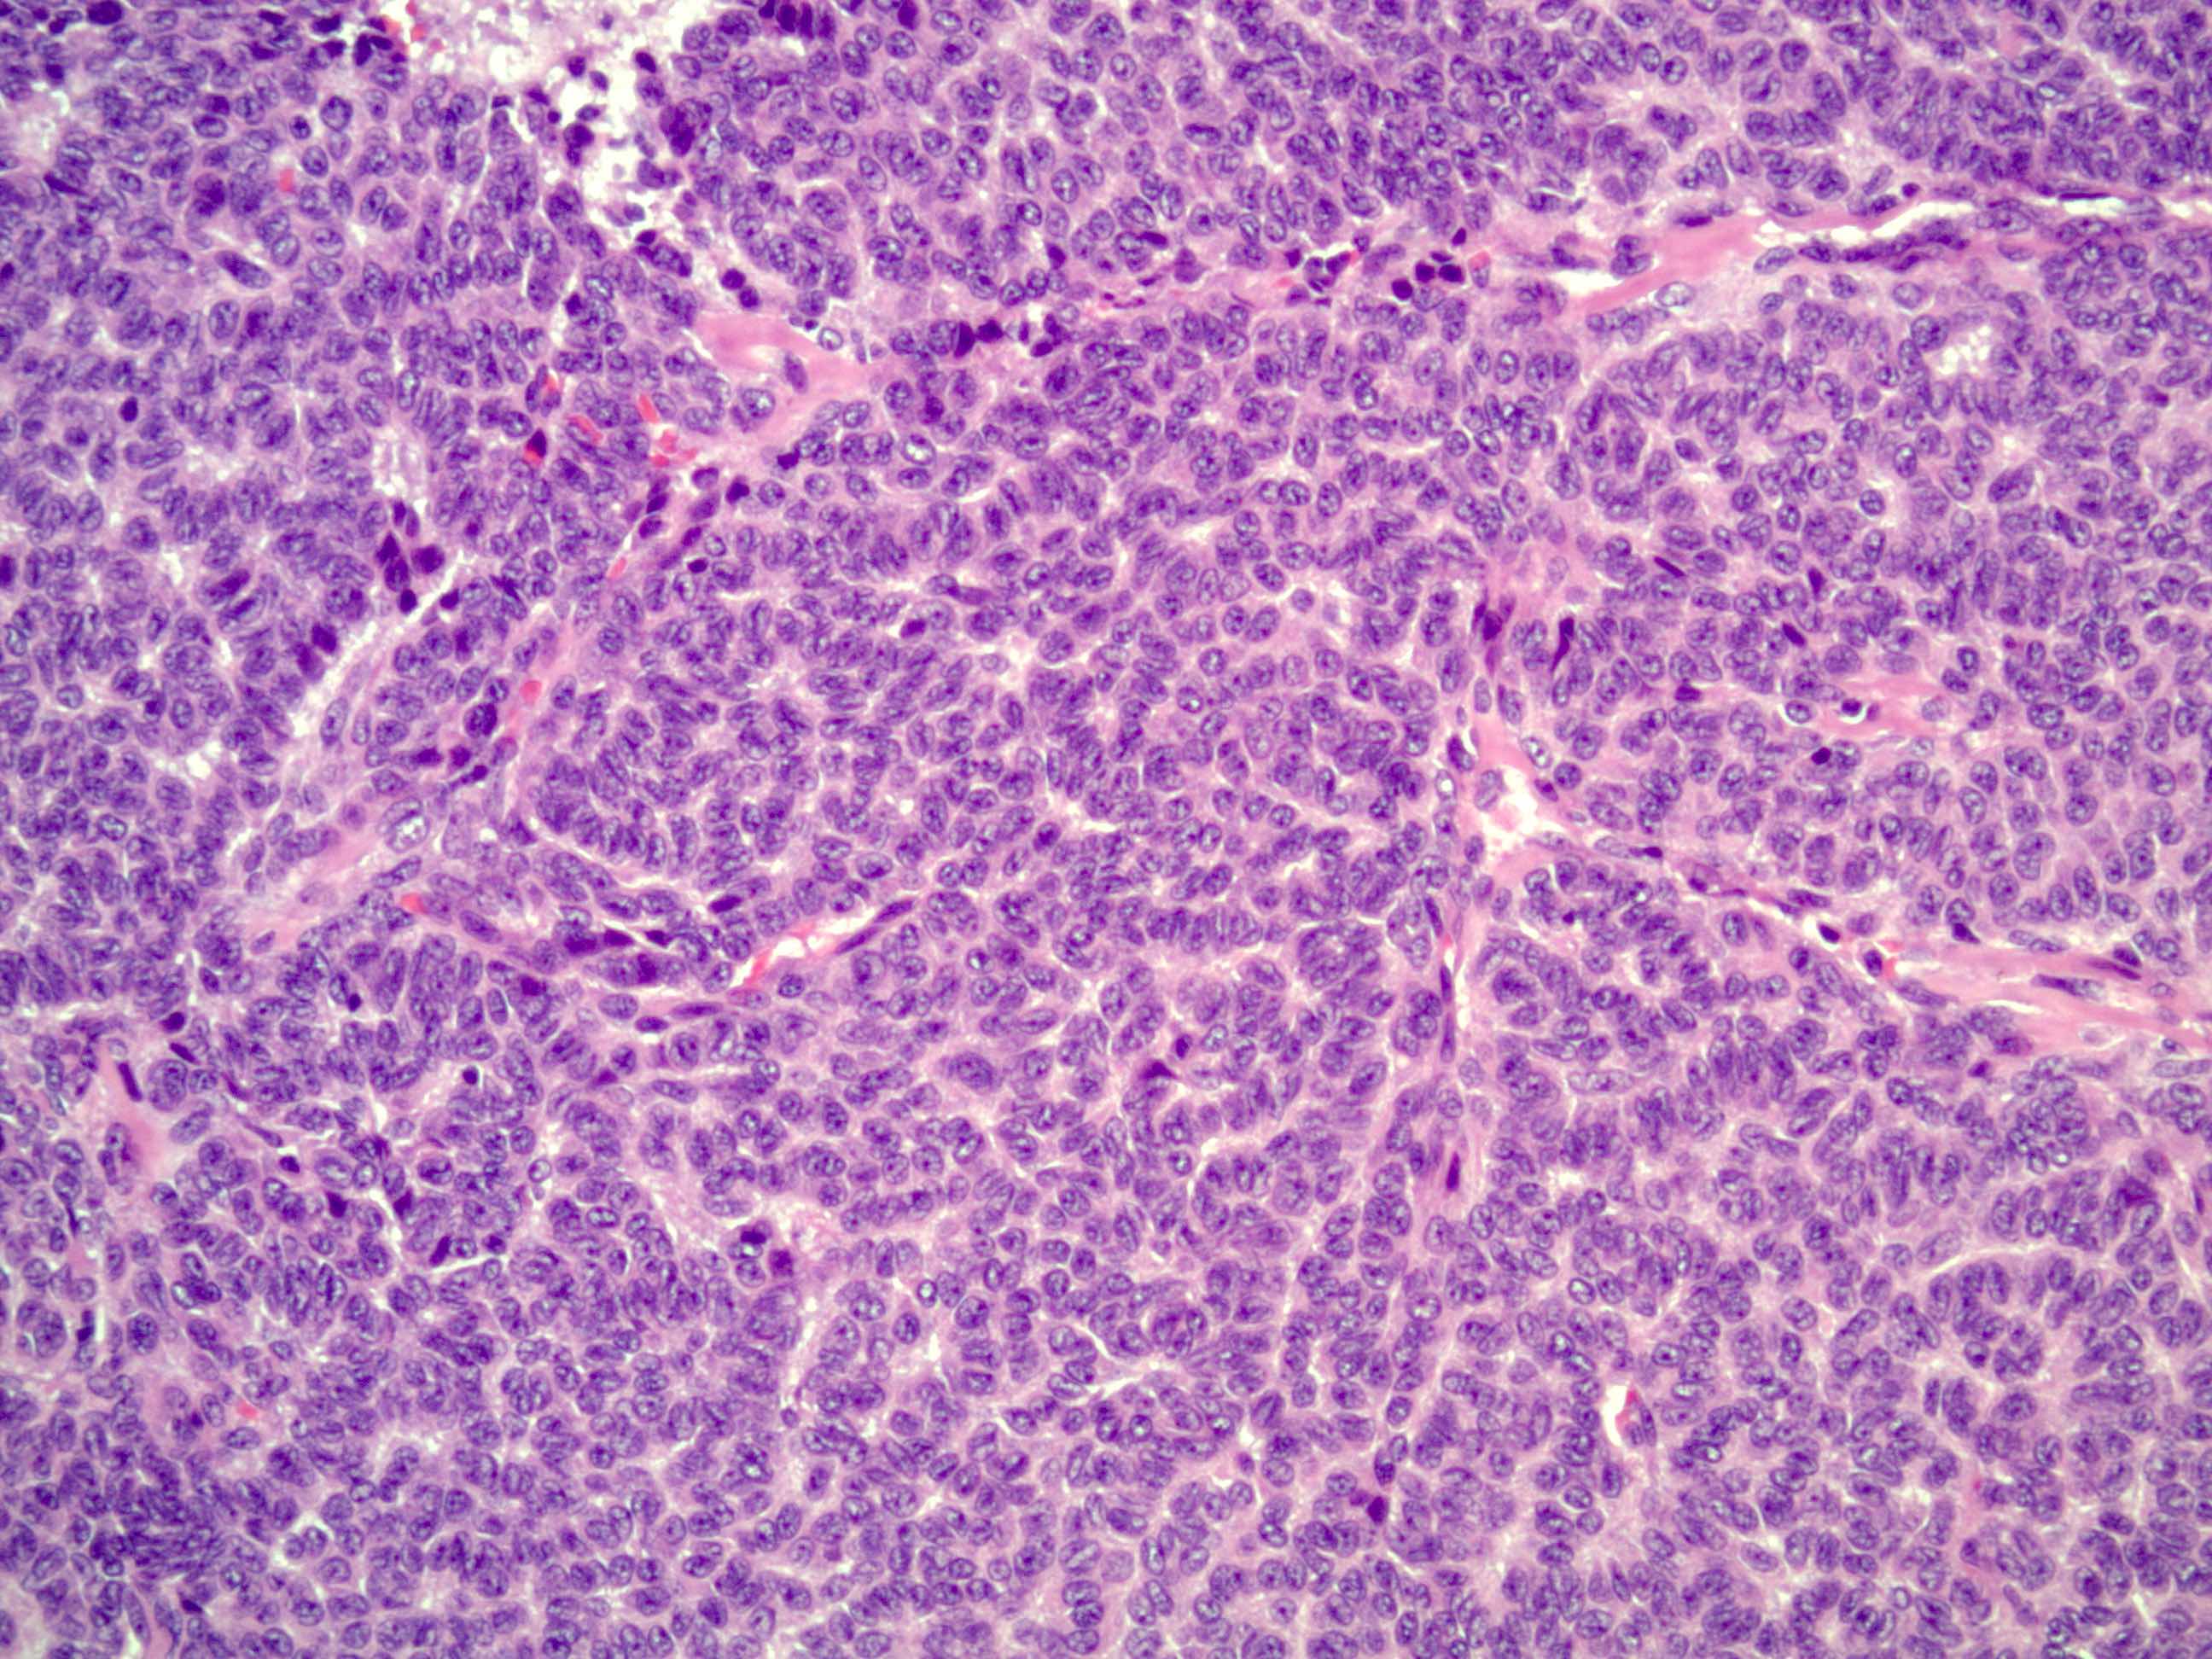

- Small, bland, cuboidal to polygonal cells with scant cytoplasm and pale, uniform angulated and usually grooved nuclei (coffee bean)

- Various patterns, including diffuse (the most common), trabecular and corded, insular, microfollicular (resembling Call-Exner bodies of the Graafian follicles: small follicle-like structures filled with eosinophilic material) and macrofollicular (the least common)

- Usually a mixed growth pattern is seen

- Mitotic activity is usually not brisk (< 3/10 high power fields)

- Stroma is usually hypervascular with variable amounts of fibroblasts and theca cells

Microscopic (histologic) images

Contributed by Shabnam Zarei, M.D. and Sharon Bihlmeyer, M.D.

AFIP images